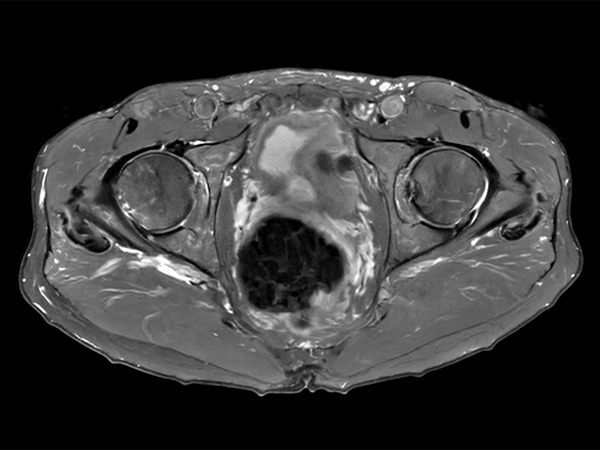

Fast bilateral hips, with SmartSpeed Precise

Fast bilateral hips_MR 5300_R11